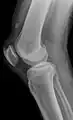

| An x-ray demonstrating quadriceps tendon rupture. Note the abnormal angle of the patella and soft-tissue swelling marked by the arrow. | |

A quadriceps tendon rupture is a tear of the tendon that runs from the quadriceps muscle to the top of the knee cap.[1]